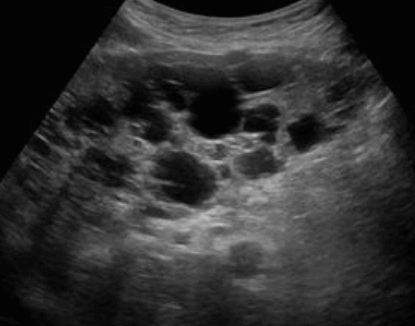

US finding

- 다양한 크기로 다발성

- 다수 발생 시 간종대 발생

- 60~70% 다낭성 신질환과 동반된다

- 낭종벽에 석회화 동반

- 격막이 형성되어 있다

polycystic liver disease ③ bile duct hamartomas